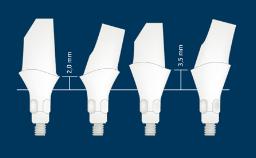

Prosthodontic Planning and Procedures

Abutment Selection for Fixed Dental Prostheses

Learning Module